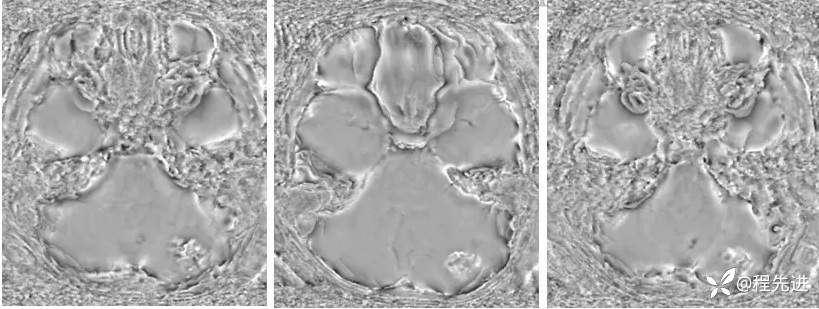

【患者信息】:男,6岁

【主诉】:查体发现左侧小脑半球占位3个月

【现病史及既往史】:患者3个月前因鼻塞至外院就诊,行头颅CT检查偶然发现颅内占位

【检查】